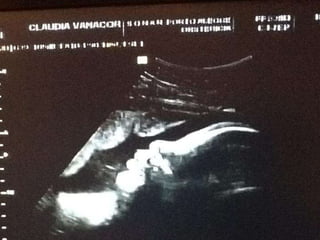

Ter uma família representa apoio incondicional de pessoas que querem seu bem-estar. Família oferece refúgio, segurança e conforto, sendo o reflexo do que a pessoa é e se tornará. Estar entre pessoas afetuosas e queridas que te amam, mesmo sendo diferentes, traz grande bem-estar à alma.